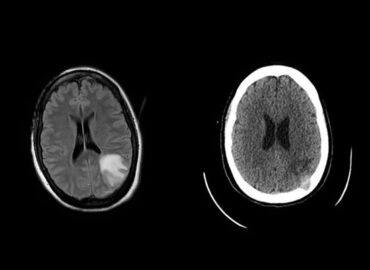

Paciente masculino de 33 años que ingresa por GC con cuadro de cefalea, visión borrosa y mareos de tres […]